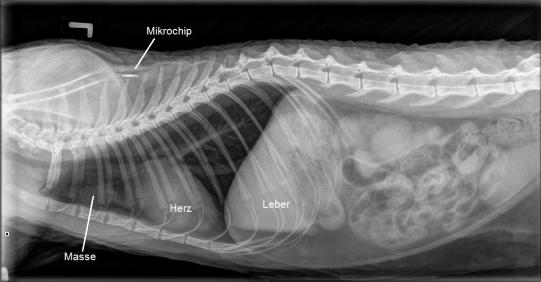

Eine Röntgenaufnahme des Brustkorbs von Nelson zeigt tatsächlich eine vor dem Herzen gelegene Masse. Genau in dieser Region liegt auch der Thymus - ein Organ, in dem beim Embryo und Welpen Abwehrzellen ausgebildet werden. Beim älterwerdenden Tier verschwindet der Thymus in aller Regel vollständig.